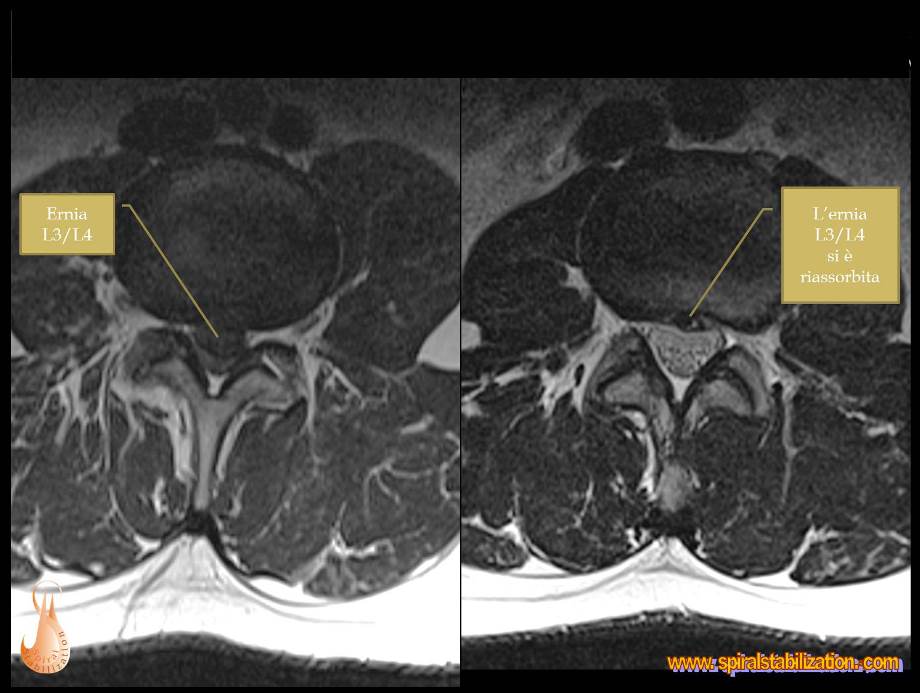

1 - Ernia L3/L4

B - 1 - 1 -1

Ernia del disco L3/L4